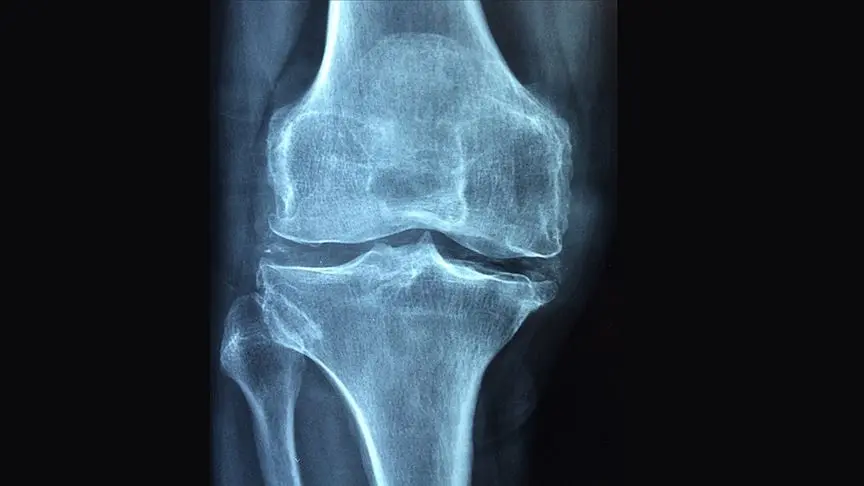

Çin’deki bir araştırma ekibi, kırık kemikleri metal plakalar ve vidalara gerek kalmadan sabitlemeyi amaçlayan yeni bir biyolojik yapıştırıcı geliştirdi. “Bone-02” adı verilen bu yapıştırıcı, deniz istiridyelerinin kayalara tutunma mekanizmasından esinlenerek tasarlandı.

Üniversitenin açıklamasına göre, yapıştırıcı kırık bölgeye enjekte edildiğinde parçaları 2-3 dakika içinde sabitleyebiliyor. Ancak bu, kemiklerin tamamen iyileştiği anlamına gelmiyor. Klinik deneylerde hastaların tam iyileşme süresi yaklaşık üç ay olarak bildirildi.

Laboratuvar testlerinde Bone-02’nin 181 kilodan fazla yük taşıyabildiği, kanlı ve ıslak ortamlarda bile etkili olduğu ve vücut tarafından emilebildiği açıklandı. Böylece metal implantların çıkarılması için ikinci ameliyata ihtiyaç kalmıyor.